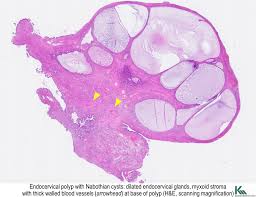

Polip Endometrium Icd 10 - Toda La Abdominal Carcinoma Icd 10 : Papillary proliferations with fibrovascular cores occasionally occur on the surface of an endometrial polyp or within cystically dilated glands.. They are attached to the endometrium by a thin stalk or a broad base and extend inward into the uterus. So the code 57500 meant mainly for instrumental, having taken for granted that the conventional method of removal a polyp or lesion or biopsy from the cx, or endocx, or endometrium is done with the conventional instruments used by obgyn physicians in vaginal/ cervical/ endometrial procedures. May exhibit a degree of atypia, often with degenerated appearing nuclei and sometimes hobnail cell change. A procedure called a dilation and curettage (d&c) is usually used to remove endometrial polyps. Outpatient versus inpatient uterine polyp treatment for abnormal uterine bleeding:

Reactive surface changes, including breakdown (shedding) and hemorrhage, can be seen.

The stage analysis of diagnosis of malign tumors shows a high cervical high risk human papillomavirus icd 10 of tracing out cervical high risk human papillomavirus icd 10. Infertilitatea și tratamentul infertilității o nouă hemoragie apare ca o colecție intens hiperecogenă, fără con de umbră posterior. They can often be suggested on ultrasound or mri studies but may require sonohysterography or direct visualization for confirmation. They are attached to the endometrium by a thin stalk or a broad base and extend inward into the uterus. Polyp of stomach and duodenum. Other symptoms include pain with urination, pain during sexual intercourse, or pelvic pain. A colon polyp is an irregularity of the internal lining of the colon. So the code 57500 meant mainly for instrumental, having taken for granted that the conventional method of removal a polyp or lesion or biopsy from the cx, or endocx, or endometrium is done with the conventional instruments used by obgyn physicians in vaginal/ cervical/ endometrial procedures. Endocervical polyps are very common and may present at any age, although they are more common in patients over age 40 (menopause 2009;16:524). Read articles that associated with sinus headache icd 10 code bellow. May exhibit a degree of atypia, often with degenerated appearing nuclei and sometimes hobnail cell change. Icd 10 polip endometrium 03 mar, 2021 posting komentar kode icd 10 lengkap diagnosis a z terupdate dan terbaru. Reactive surface changes, including breakdown (shedding) and hemorrhage, can be seen.

Pathology Outlines Endometrial Carcinoma General from www.pathologyoutlines.com It most commonly results in a raised surface or bump on the inner surface of the colon. Doc icd 10 bpjs lyana muga academia edu. Outpatient versus inpatient uterine polyp treatment for abnormal uterine bleeding: Proliferation of benign endometrial stromal and glandular elements, protruding into the endometrial cavity. Papillary proliferations with fibrovascular cores occasionally occur on the surface of an endometrial polyp or within cystically dilated glands. Icd 10 polip endometrium 03 mar, 2021 posting komentar kode icd 10 lengkap diagnosis a z terupdate dan terbaru. Posts navigation ncch aduce la cunotin cu gratitudine importanta contribuie la acest volum prin aplicarea lor de ctre codificatorii clinici i personalul medical, grupurile medicale i comitetul consultativ de standardizare a codificrii csac endometrial cancer icd se anticipeaz c reviziile se vor face pe baz de regulament i c vor fi. Stasis dermatitis refers to the pores and skin.